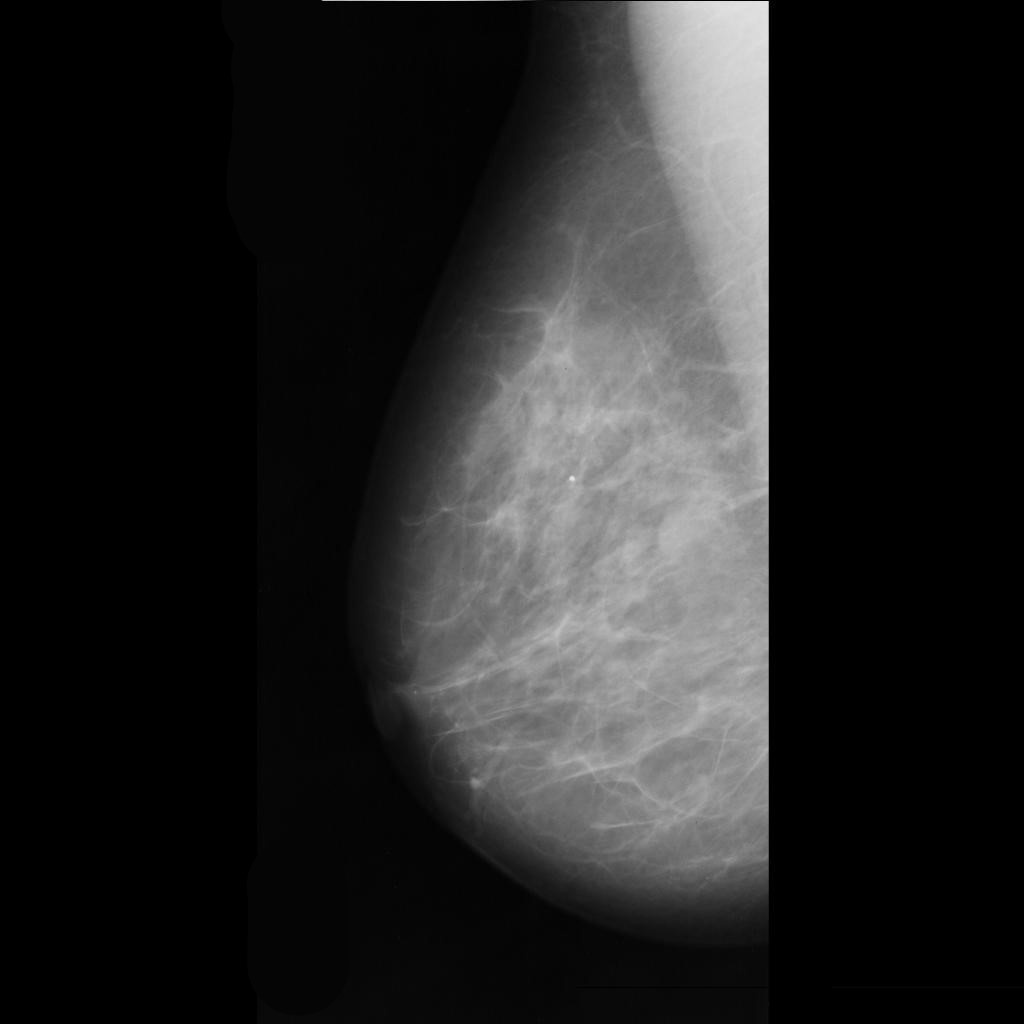

benign